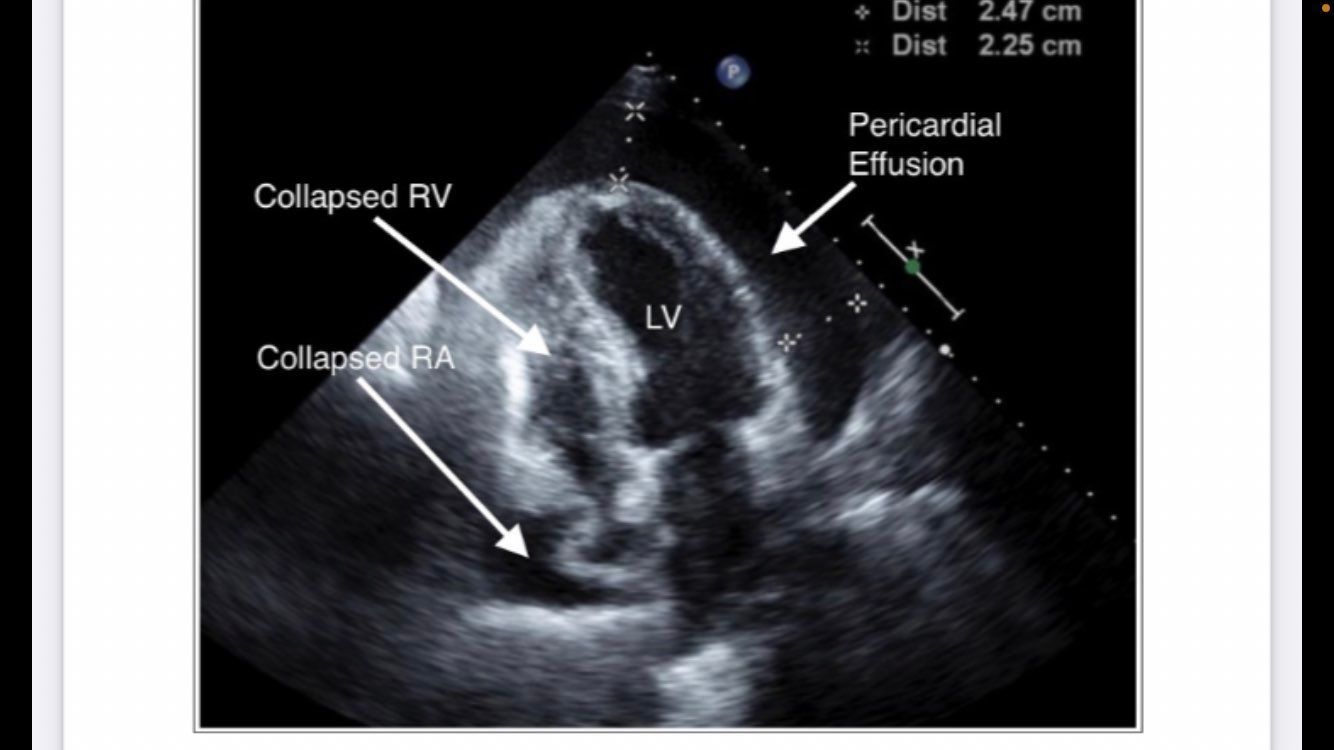

TTE IMAGE OF TAMPONADE